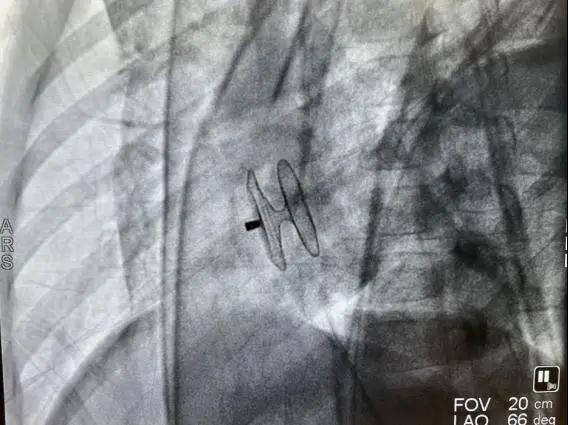

此次手术由副主任贾鹏主刀,在多学科团队共同协作下,顺利建立静脉轨道,经9F输送装置,于房间隔缺损处成功植入24mm MemoCarna氧化膜单铆ASD封堵器1枚,仅35分钟顺利完成手术。

(MemoCarna氧化膜单铆ASD封堵器X线下图像)

复查心脏彩超显示:封堵器形态、位置正常,与房间隔高度贴合,缺损封堵完全,未影响周边瓣膜运动;心电图正常。